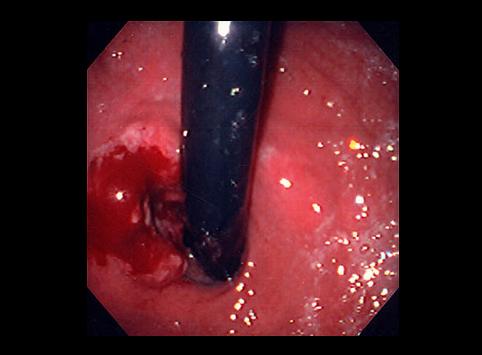

Criteria of Hist.ClassificationMalignant epithelial tumor/Adenocarcinoma

LocationStomach/Gastroesophageal junction

Technique, MethodEndoscopy

Macroscopic TypesType 2 Ulcerated type with clear margin/

Size30 - 34

Depth of Tumor Invasionsubserosa (subadventitia)